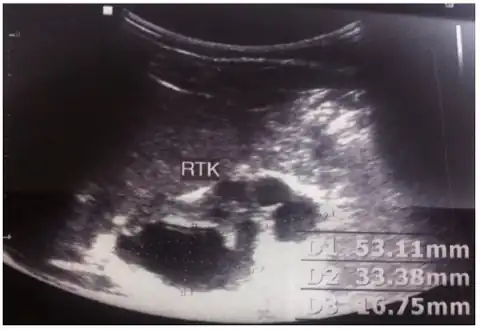

MCDK is usually diagnosed by ultrasound examination before birth. Mean age at the time of antenatal diagnosis is about 28 weeks[10] A microscopic analysis of urine in individuals with probable multicystic dysplastic kidney should be done.[8]One meta-analysis demonstrated that unilateral MCDK occurs more frequently in males and the greater percentage of MCKD occur on the left side of the body.[11]

Right dysplastic kidney with the largest cyst size measuring 33.16mm -